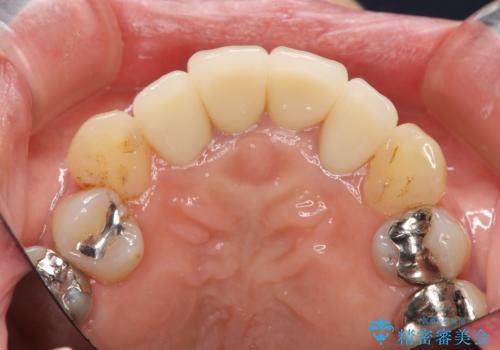

劣化したクラウンを除去し、再発した虫歯を徹底的に除去したのち根管治療・ファイバーコア築盛を行いジルコニアクラウン製作へと移ります。

- 52万円(仮歯・ファイバーコア・ジルコニアクラウン×4)費用は治療当時の料金となります